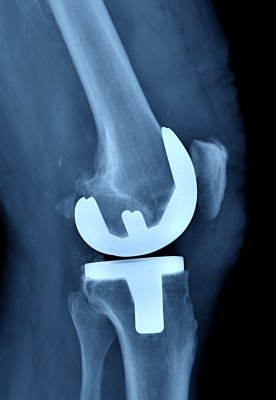

В Балахнинской ЦРБ начали выполнять операции по замене коленных суставов

Уже успешно проведены пять таких процедур. В Балахнинской ЦРБ начали выполнять операции по замене коленных суставов.

Чаще всего артроз развивается из-за лишнего веса, перенесённых вирусных инфекций, сверхнагрузок, влияет и наследственность. После замены сустава исчезает боль, восстанавливается объём движений в суставе и способность опираться на ногу.

В больнице пациенты проводят не более недели, реабилитация после замены суставов занимает около 3-4 месяцев. Операции проводятся бесплатно, по полису ОМС, сообщает главный редактор ИА "Стационар-пресс" Алексей Никонов.